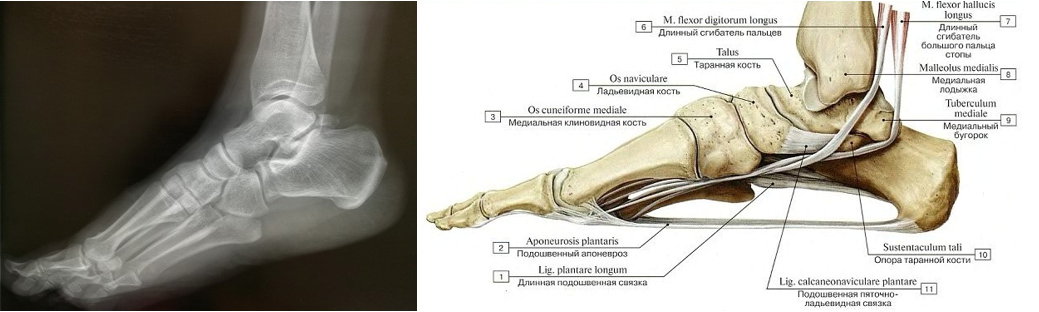

Анатомические фото голеностопного сустава и его суставных поверхностей